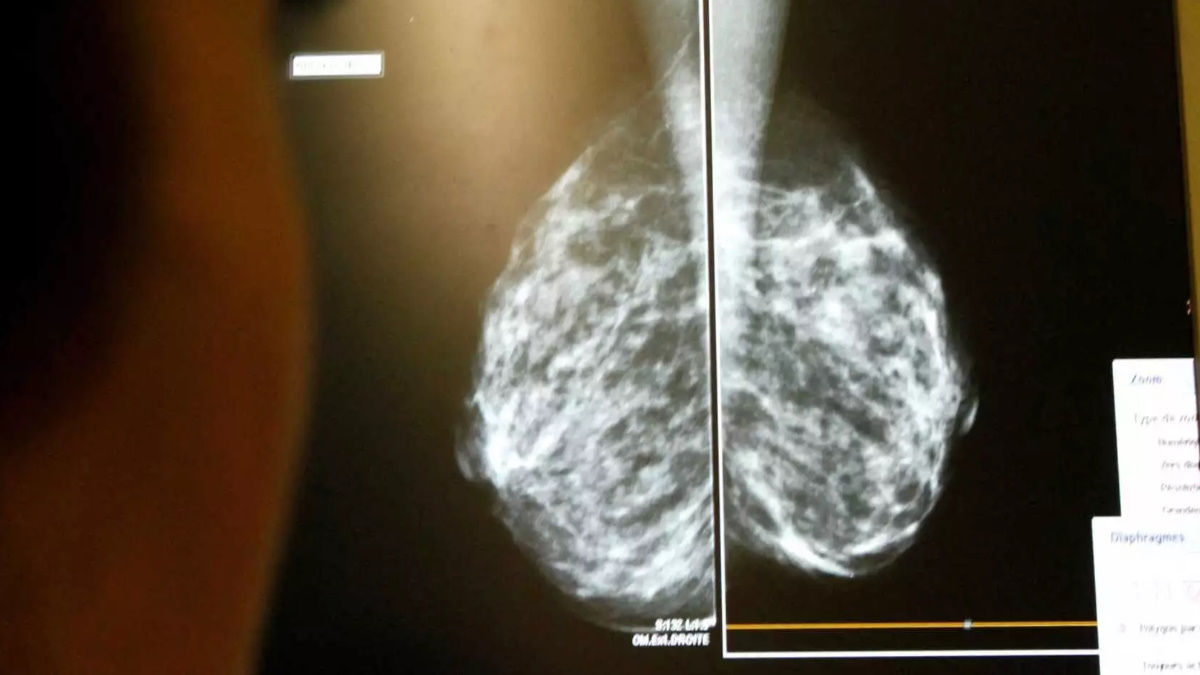

«Αντιμετωπίζουμε σήμερα και κάθε μέρα, όλο και πιο βαριά περιστατικά προχωρημένης νόσου με καρκίνο συμπαγών οργάνων, που σημαίνει βαρύτερες επεμβάσεις, πολλές φορές ακρωτηριαστικές επεμβάσεις, όπως είναι η μαστεκτομή για τον καρκίνο του μαστού, ή η παρά φύση έδρα για τον καρκίνο του ορθού», ανέφερε ο Ιωάννης Καραϊτιανός, επίκ. Καθηγητής Χειρουργικής ΕΚΠΑ, Δ/ντής Χειρουργικής Κλινικής Νοσ. «Ερρίκος Ντυνάν», Πρόεδρος της Ελληνικής Εταιρείας Χειρουργικής Ογκολογίας,

«Χρειάζεται μια νέα καμπάνια ώστε να αυξήσουμε τα ποσοστά των ασθενών οι οποίοι θα διαγνωστούν με καρκίνο σε πρώιμο στάδιο, ούτως ώστε να έχουμε μια ριζική αντιμετώπιση. Υπενθυμίζω ότι μελέτη της Ελληνικής Ομοσπονδίας Καρκίνου (ΕΛΛΟΚ) έδειξε ότι μόνο 11% των Ελλήνων ασθενών με καρκίνο διαγνώστηκαν στα πλαίσια ενός προσυμπτωματικού ελέγχου, ενός τσεκ απ δηλαδή, έναντι όλων των άλλων που διαγνώστηκαν, όταν υπήρχαν ήδη προβλήματα από τον καρκίνο», σημείωσε ο κ. Καραϊτιανός και πρόσθεσε:

Αυτό υποστηρίζει ο κ. Καραϊτιανός: “Υπάρχουν πολύ καλύτερα αποτελέσματα στα Κέντρα αυτά και στην επιβίωσή τους, και στην μείωση των ακρωτηριαστικών επεμβάσεων και στην τελική έκβαση των ασθενών αυτών. Μια χειρουργική επέμβαση, αν δεν γίνει σωστά σε έναν ογκολογικό ασθενή, οποιαδήποτε παρέμβαση στη συνέχεια-είτε ακτινοθεραπευτική, είτε χημειοθεραπευτική- δεν θα δώσει τα ανάλογα σωστά αποτελέσματα. Άρα προτείνουμε την αναγνώριση της Χειρουργικής Ογκολογίας και την εξειδίκευση σε όργανα στόχους: για τον καρκίνο του μαστού, του παχέος εντέρου του προστάτη, του ήπατος, παγκρέατος. Όσο έχουμε καλύτερη εξειδικευμένη εμπειρία σε εξειδικευμένα κέντρα τόσο καλύτερα είναι τα πράγματα”, λέει.